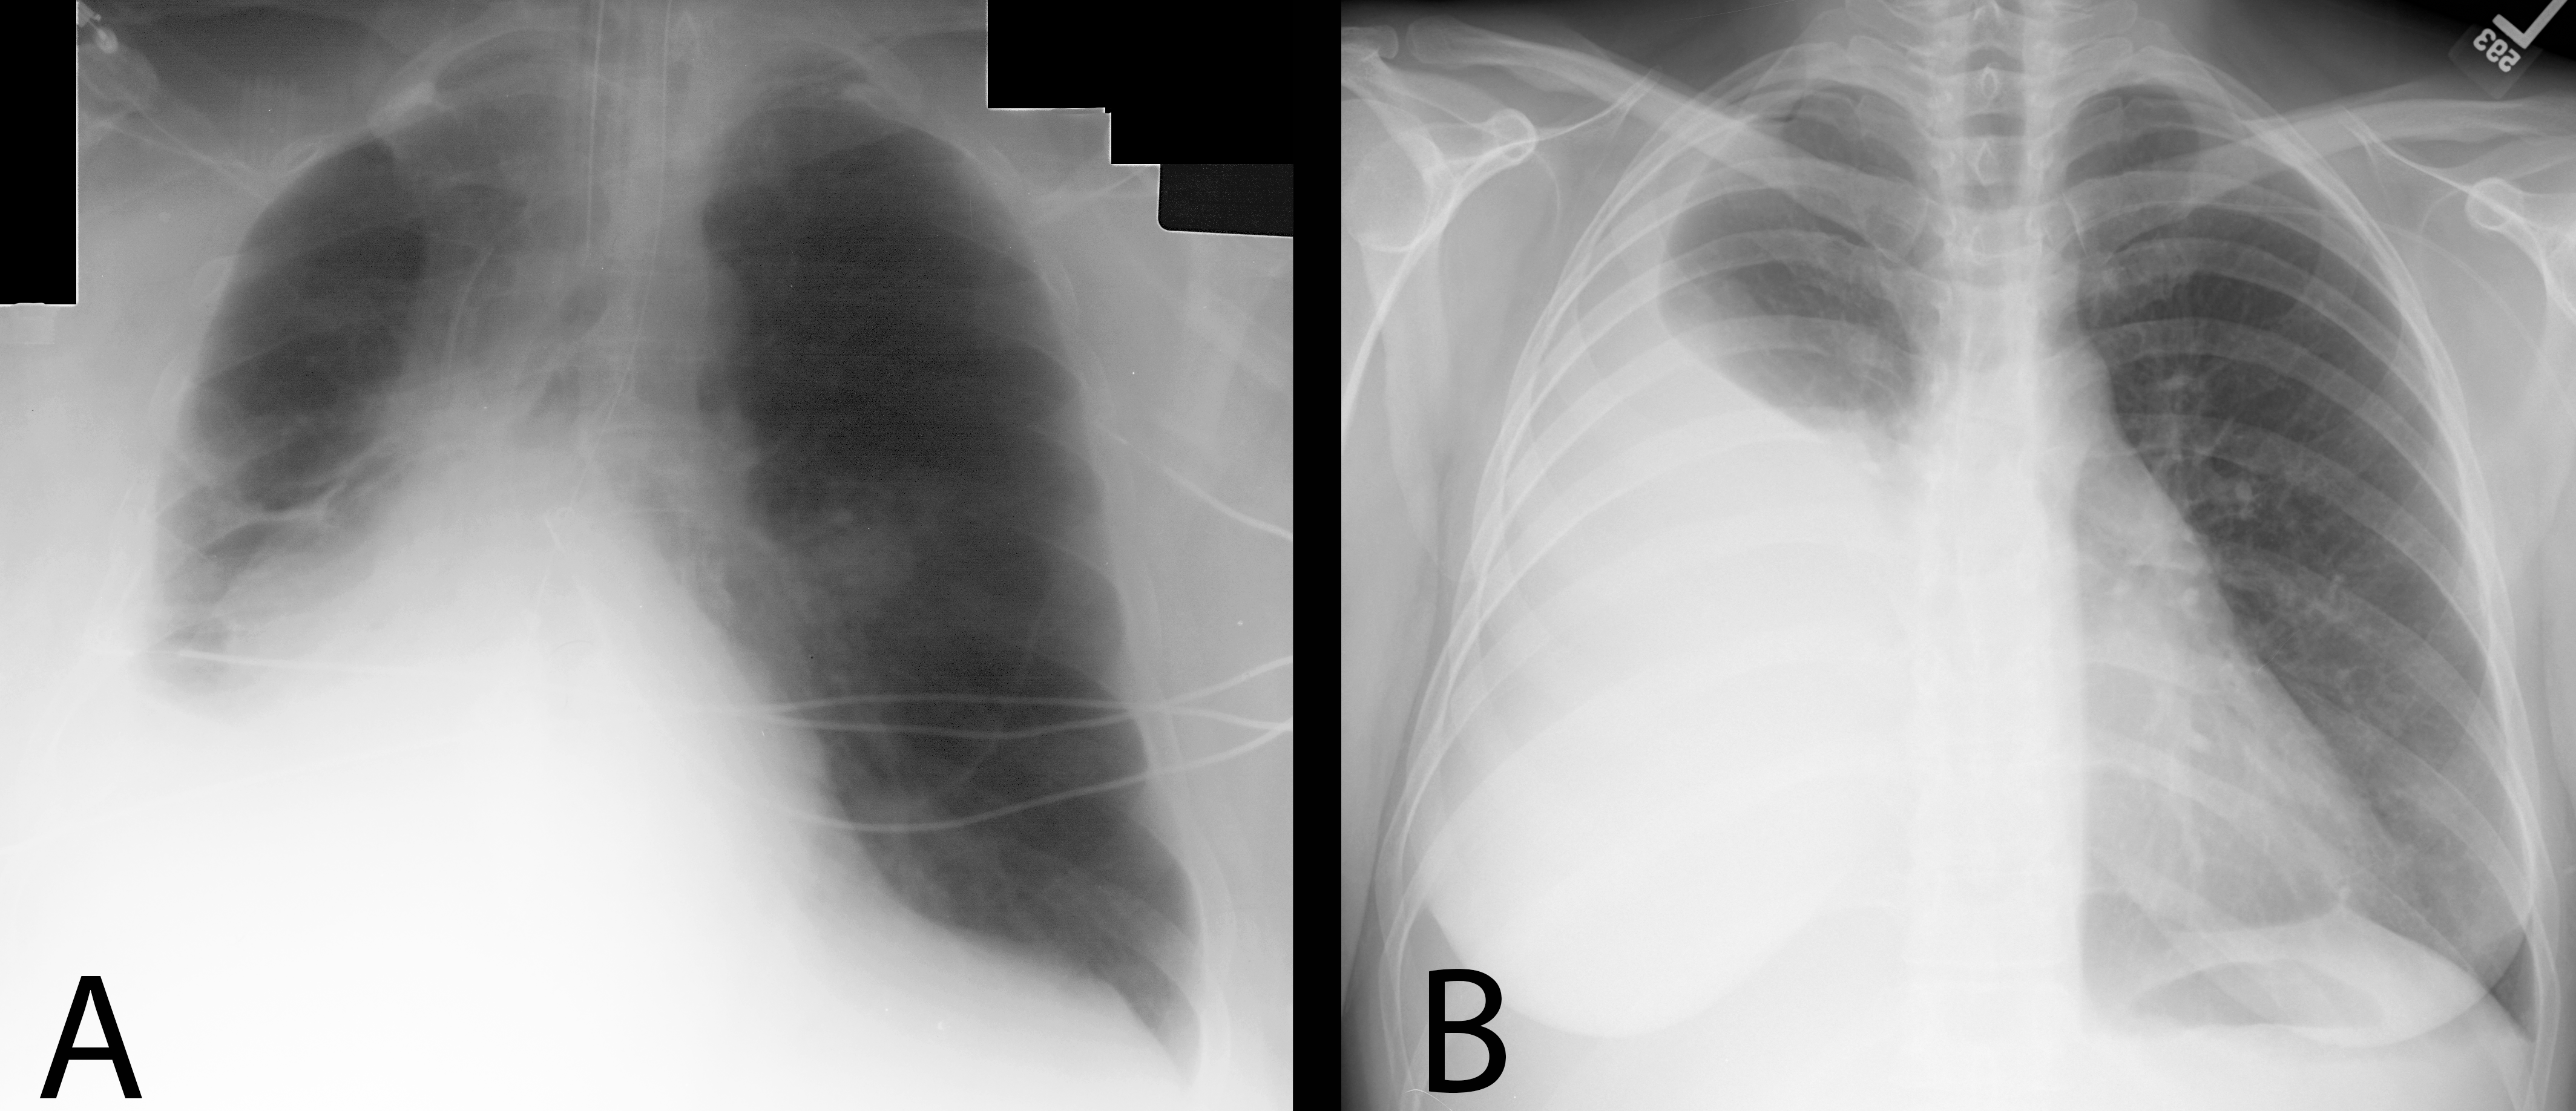

Second pair--both patients have CHF, but one has the typical appearance of acute/severe edema with an alveolar pattern, while the other has a subacute/chronic interstitial pattern.